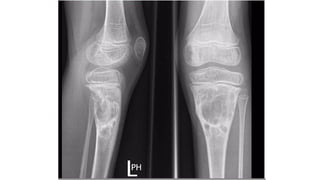

Chondromyxoid fibroma

• • 2nd and 3rd decades

• • L o c a t i o n

• • 2/3"d around the knee joint - specially proximal tibia

• (metaphyseal, may extend to epiphyseal line)

• • Can occur in fl a t and short bones

• Lobulated radiolucent, eccentric lesion

• Well-defined margin with surrounding sclerosis

• Presence of septations

• No periosteal reaction

• • Calcification very uncommon

• Sometimes, peripheral bony margin very hazy and poorly defined, appearing aggressive

• • CT is helpful to delineate a cortical margin in the expanded soft-tissue mass

• • B o n e s c a n

• • Increased activity is usually localized to the reactive sclerosis rather t h a n t o t h e lesion

itself

Plain radiograph and CT Scan features

D i ff e r e n t i a l s

• NOF - younger age group

• • Chondroblastoma - younger age group

• • ABC = ill-defined endosteal margin